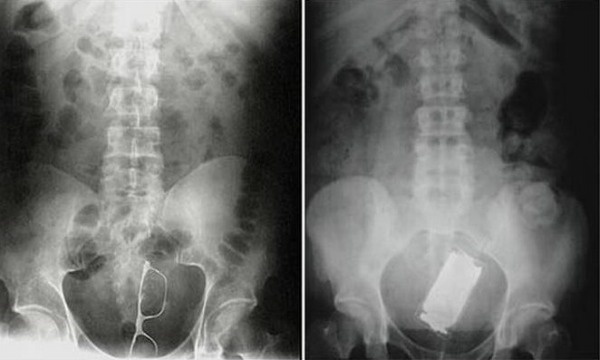

Οι πιο ασυνήθιστες ακτινογραφίες που έχετε δει

Και όταν λέμε περίεργα αντικείμενα δεν είμαστε υπερβολικοί, καθώς αυτά είναι κασέτες, ψαλίδια, κούκλες, γυαλιά κ.α.